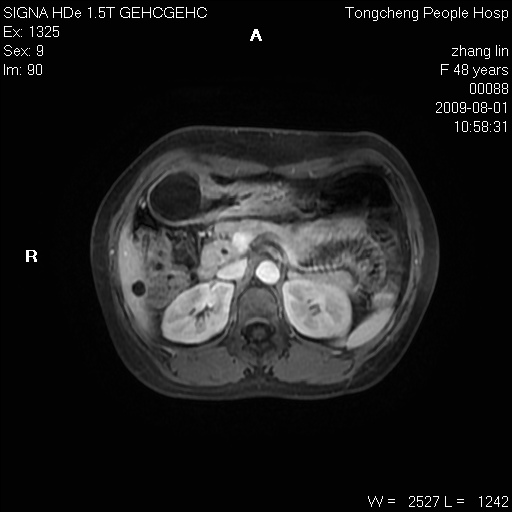

女,48岁。健康体检,彩超发现右肾占位性病变。平素健康。

临床诊断:右肾占位性病变,性质待定(囊肿?肿瘤?)。

上中腹部mr平扫+增强扫描,图像如下:

右肾上极见一类圆形病灶,t1wi呈等信号t2wi呈等高混杂信号,三期增强无强化,边界清---考虑囊肿出血。

同反相位均表现为等信号,病变无强化,考虑含蛋白的囊肿可能,弥散加权相或许有些帮助,

肝囊肿

慢性胆囊炎